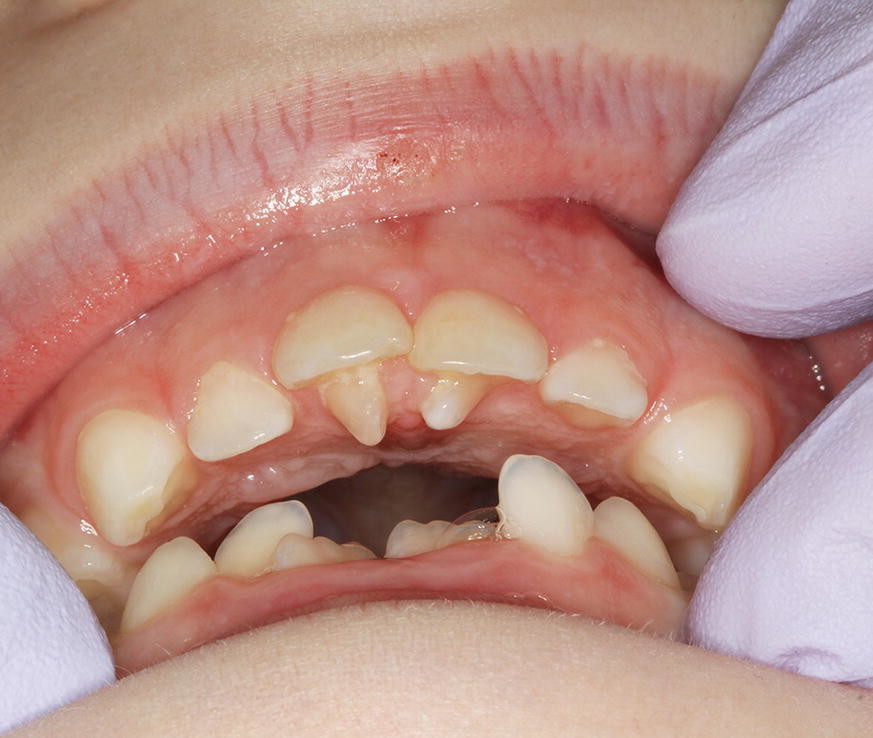

Dental anomalies, what is referred? And what should be?

Patients with complex dental anomalies can be challenging to treat. Often, with their unique dental needs, comes extensive treatment planning and multidisciplinary care. Hence, general dental practitioners (GDPs) need to have the knowledge and skill base to accurately identify and refer such patients. However, what dental anomalies are commonly referred? And how should they be managed?

In addition to the service analysis described in part 1 of the BDJ series, in part 2 the authors provide an overview of common dental anomalies. Their definition, classification, aetiology and prevalence have been outlined along with their diagnosis and management. The aim of this is to increase awareness amongst practitioner's and help them formulate appropriate treatment plans. Part 1 of the series covers soft tissue anomalies, dentigerous cysts, transpositions and supernumerary teeth. Whereas part 2 focuses on impacted teeth, delayed and failed eruption, ankylosed incisors and infra-occluded deciduous molars.

Dental anomalies are often asymptomatic and may develop from an early age, the GDP therefore has a crucial role in early identification and management. In addition, dental anomalies often require onward referral to a specialist for management and so knowledge of potential management strategies will aid the GDP in counselling patients.